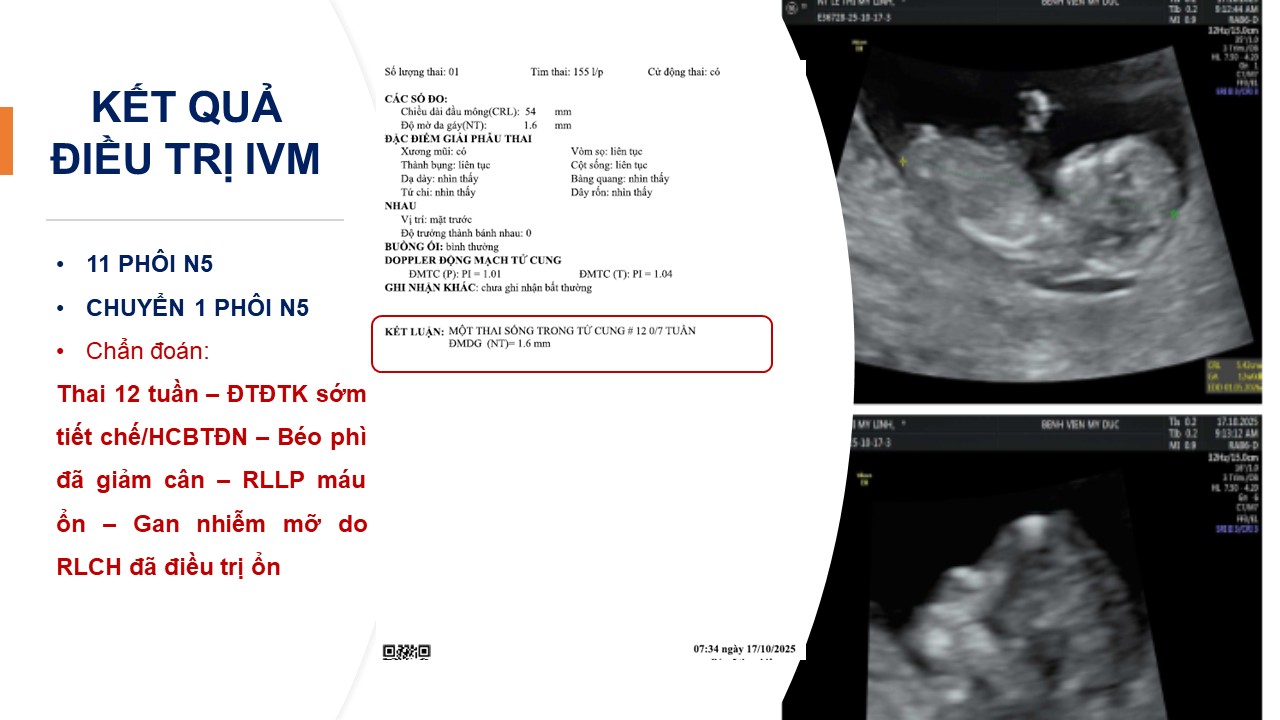

Góc nhìn thực tiễn ca lâm sàng: Chiến lược quản lý toàn diện béo phì trước HTSS - phối hợp đa chuyên khoa